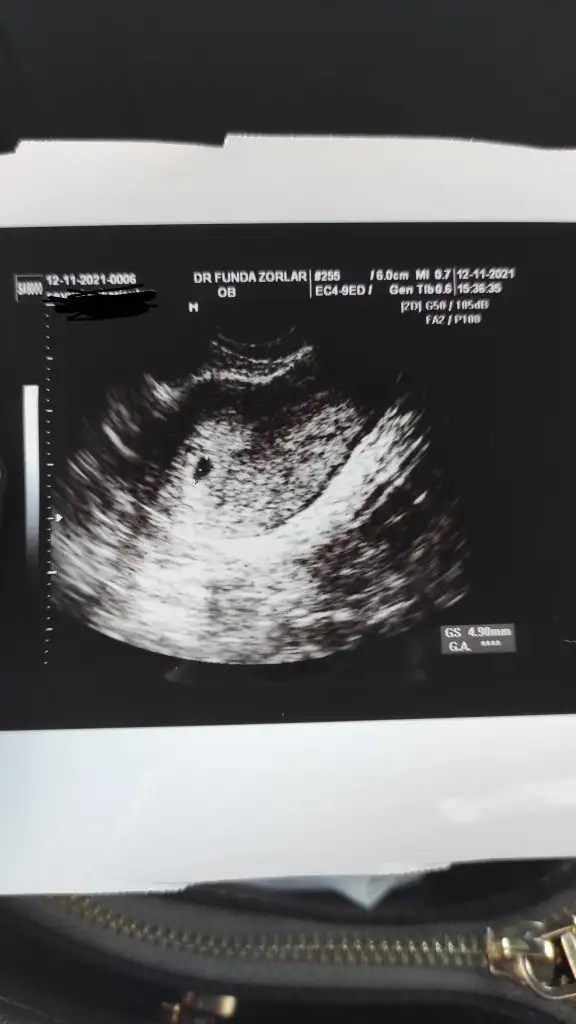

Ultrasonu ekledim aşağıya kaç yazdığını göremedimCanım hayırlı olsun ultrasona göre kaç haftalıkmış ? Yazıyor mu ultrason kağıdının üstünde?

Geçen cumartesi doktorum 10 mm demişti bugün 18 mm dediMerve2401 Birde boş gebelik demesi için kese boyutu önemli belli bir boyuta gelmiş olan kesede bebek izlenmeli eğer ulaşmadiysa normal görülmemesi.